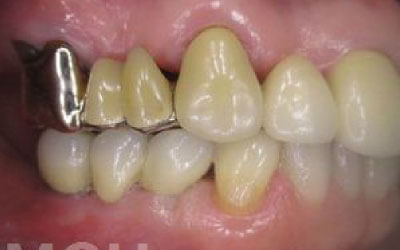

ブリッジとインプラントでは、支えとなる歯の寿命に大きな違いがあります。ブリッジは支えの歯を虫歯でなくても大きく削る必要があり、さらに噛む力が通常の約1.5倍かかるため、その歯の寿命が短くなってしまいます。実際の統計によると、ブリッジの支えとなる歯は10年以内に約68%が抜歯に至っています。

私たちが噛むとき、歯には何十キロもの力がかかっています。そのため、歯の本数が減るほど、残った歯にかかる負担は大きくなります。ブリッジ治療の場合も、失った歯にかかっていた力を前後の健康な歯が支えることになります。その結果、残っている歯には、抜歯前よりも1.5倍から2倍ほど強い力がかかるのです。

ブリッジなどの治療では、支えとなる前後の歯を大きく削らなければなりません。場合によっては、虫歯でなくても歯の神経を抜くことがあり、神経を抜いて被せ物をすると、その歯は急速に寿命が短くなってしまいます。一方でインプラント治療は、前後の歯を削ったり神経を取ったりする必要がありません。健康な歯をできるだけ残すことは、歯の寿命を延ばすために非常に重要です。

最も大きな違いは、前後の歯の寿命が変わることです。

ブリッジは、抜けた部分の前後の歯を大きな虫歯と同じくらい削る必要があります。

さらに、抜けた歯の力を前後の歯が負担するため、ブリッジを支える歯には常に1.5倍の力がかかります。

1)ブリッジ

2)歯を大きく削る+支えの歯に1.5倍の力がかかる

3)前後の歯の寿命が著しく減る

ブリッジの支えの歯は、データでは10年以内に68%が抜歯になります。